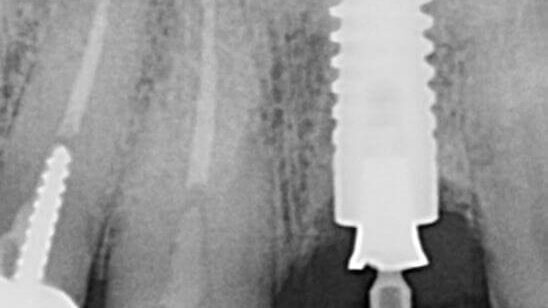

Accidental Iatrogenic Placement of Four Trilobe Locator Abutments into Nobel Conical Implants – 0028

This case illustrates an example of an Accidental Iatrogenic Placement of Four Trilobe Locator Abutments into Nobel Conical Implants.